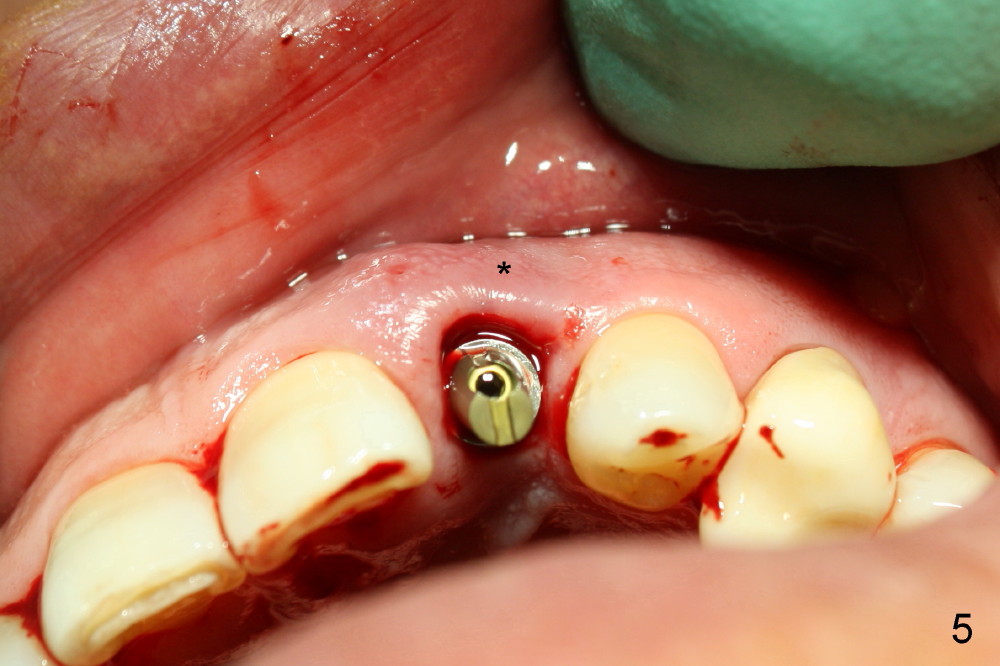

2. Try in post, cement

3. Gingival retraction cord #2, can be overlapped, stop bleeding, push gingiva away from prep, and most important prevent Titanium shaving from being trapped in socket

4. Rinse off metal shaving with normal saline or other before cord removal, bone graft or cementation of the provisional

7. Remove excess cement thoroughly